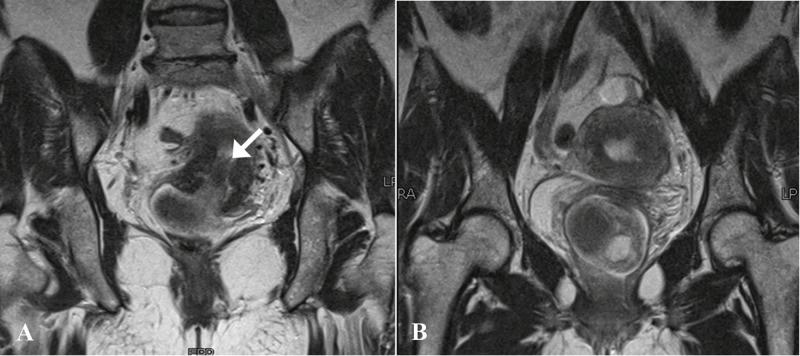

Polypoid adenomyoma is a rare uterine endometrial polypoid tumor of mixed epithelial and mesenchymal origin. Although the clinical and pathologic features of polypoid adenomyomas have been described extensively, imaging findings for these tumors have not been frequently reported in the literature. On imaging, their features may be confused with prolapsed leiomyomas or malignancy. Hemorrhagic cystic spaces in a prolapsed uterine tumor within the vagina should raise consideration of a diagnosis of polypoid adenomyoma. Such blood-containing cystic spaces would be unusual findings in leiomyomas and malignancy. Diagnosing polypoid adenomyoma is vital because it can potentially be managed by hysteroscopic resection, unlike an ordinary form of adenomyosis.

息肉样腺肌瘤是一种罕见的起源于上皮和间充质混合的子宫子宫内膜息肉样肿瘤。尽管息肉样腺肌瘤的临床和病理特征已被广泛描述,但这些肿瘤的影像学表现尚未在文献中频繁报道。在影像学上,它们的特征可能与脱垂的平滑肌瘤或恶性肿瘤相混淆。阴道内脱垂的子宫肿瘤中出现出血性囊性间隙应考虑息肉样腺肌瘤的诊断。这种含血的囊性间隙在平滑肌瘤和恶性肿瘤中是不常见的表现。诊断息肉样腺肌瘤至关重要,因为与普通形式的子宫腺肌病不同,它有可能通过宫腔镜切除术进行治疗。